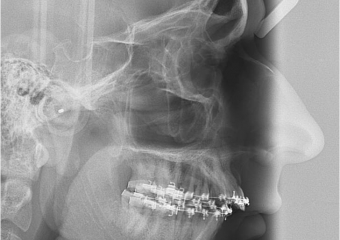

Telerradiografia inicial